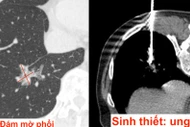

Bệnh nhân mắc 3 ung thư tiêu hóa hiếm gặp được cứu sống sau phẫu thuật phức tạp kéo dài hơn 13 tiếng, với sự phối hợp nhiều chuyên khoa.